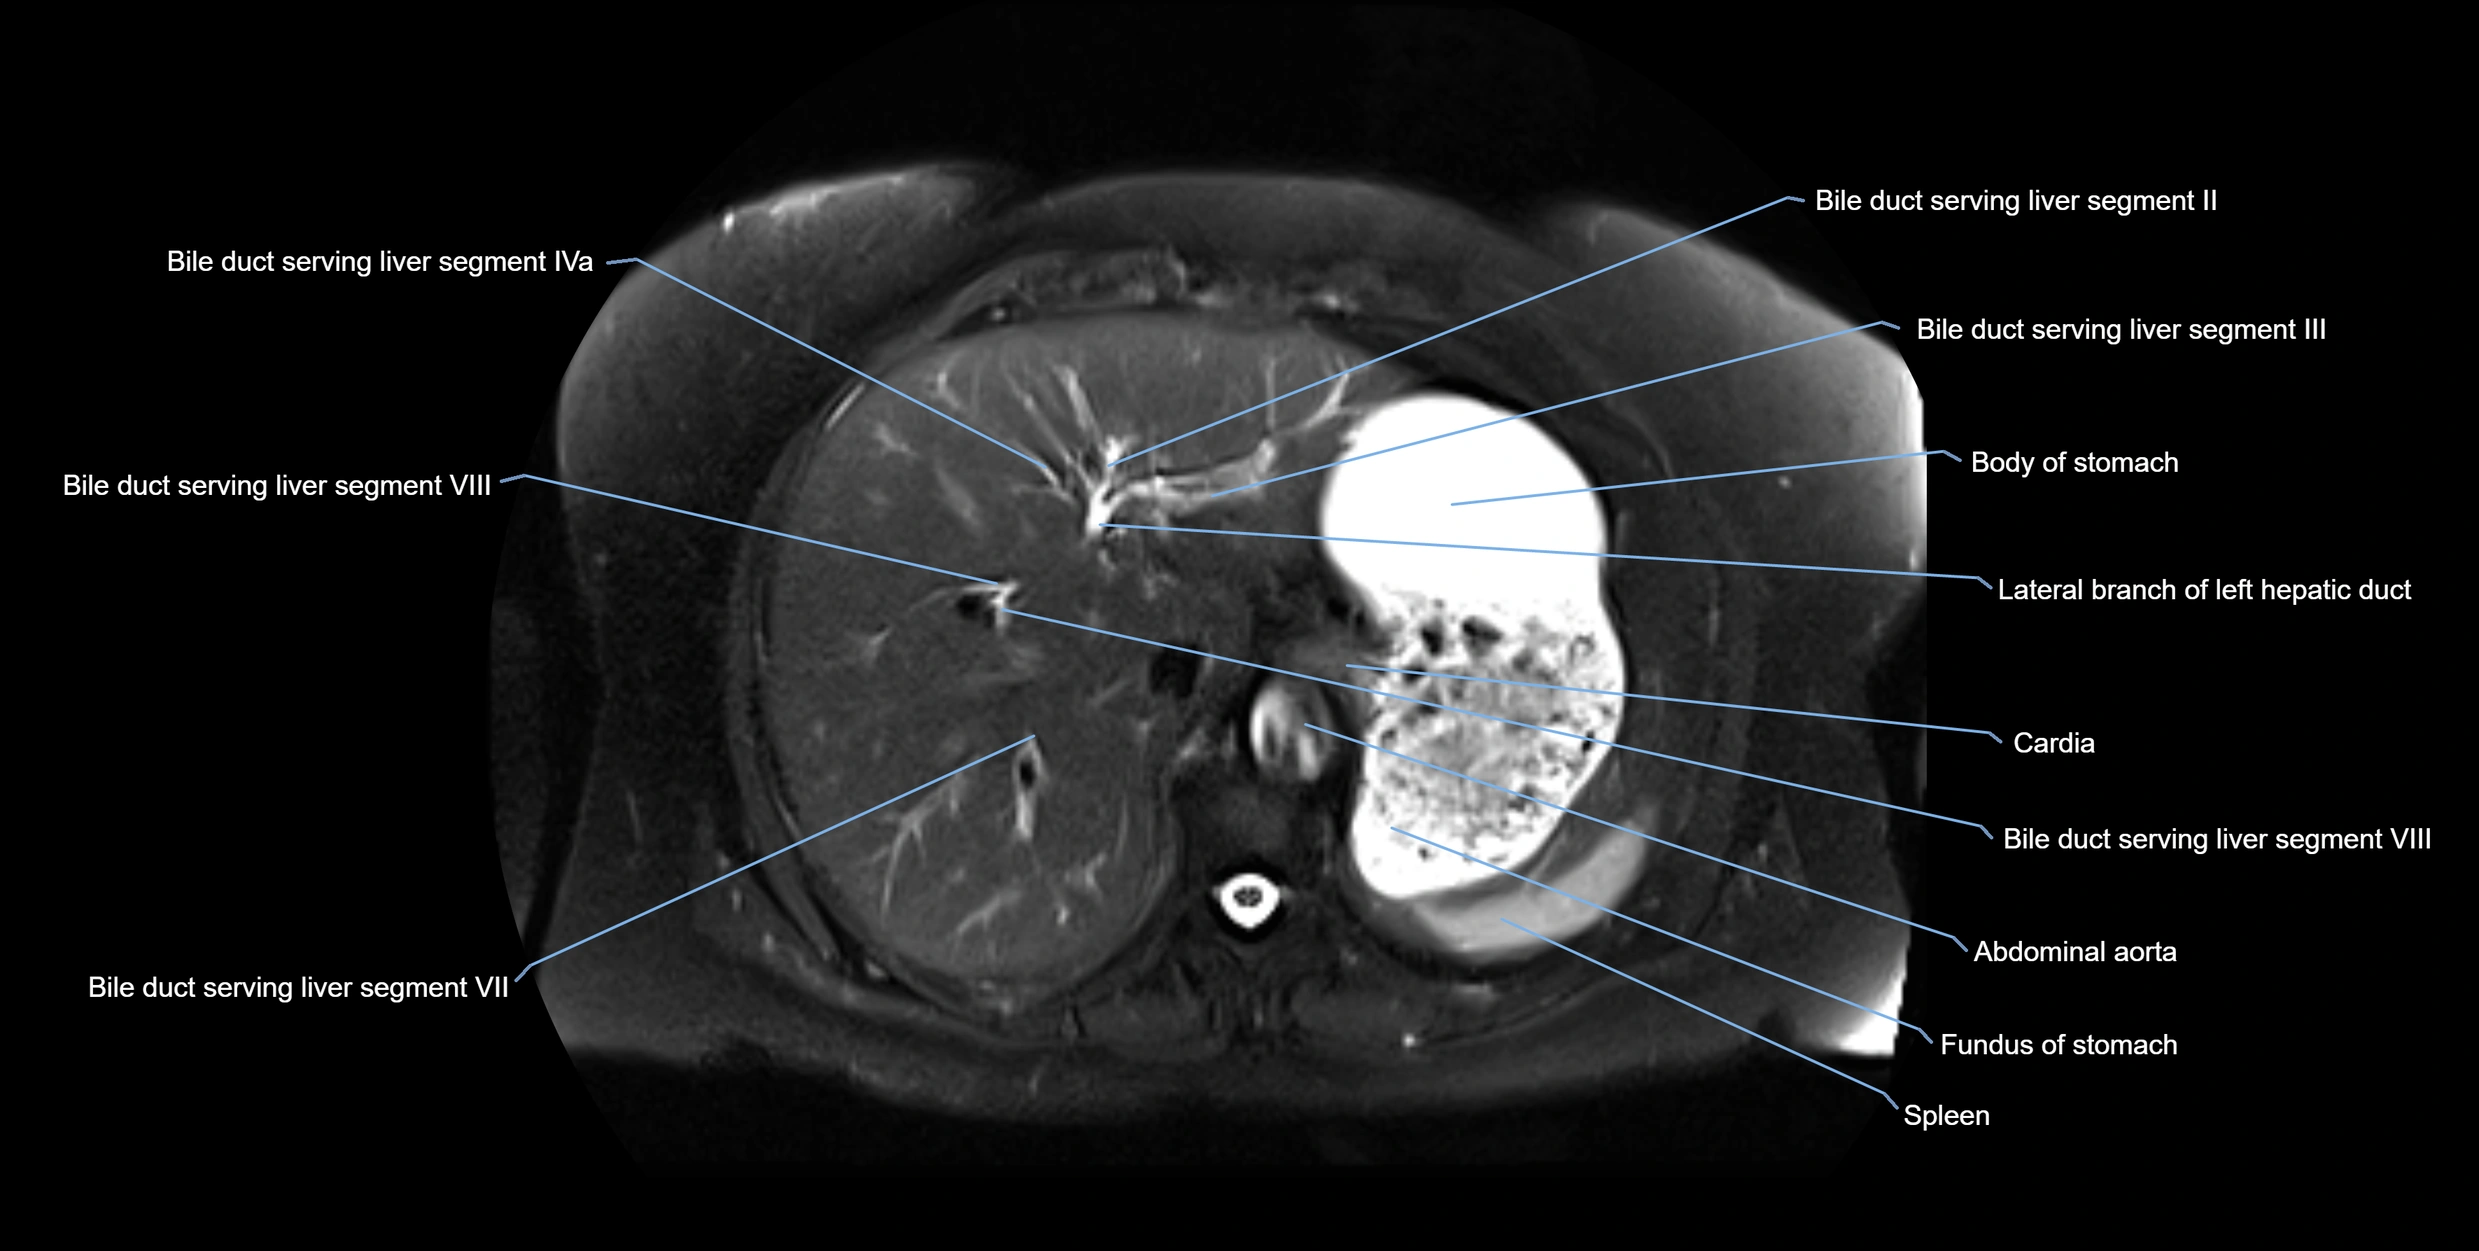

MRI Appearance

T1-weighted images:

• Not typically visualized unless dilated; appears as low signal tubular structure if seen

• Surrounding pancreatic parenchyma shows intermediate signal

T2-weighted images:

• Duct fluid appears bright

• Accessory duct seen as a fine high-signal tubular structure in pancreatic head

STIR (Short Tau Inversion Recovery):

• Duct fluid remains bright

• Surrounding fat suppressed, improving duct conspicuity

T1 Fat-Sat Post-Contrast:

• Normal duct does not enhance

• Surrounding inflammatory or neoplastic changes may enhance

T2 Fat-Saturated HASTE (single-shot):

• Accessory duct: bright, thin linear structure in pancreatic head

• Stones, strictures, or air bubbles appear as dark filling defects

• Excellent for rapid evaluation of duct patency

T2 TSE Fat-Saturated 3D (MRCP sequence):

• Duct visualized as a continuous bright tubular structure joining or parallel to the main pancreatic duct

• Allows 3D reconstruction of ductal anatomy and variants

• Excellent for diagnosis of pancreas divisum

Thick-slab T2 Fat-Saturated HASTE:

• Shows the accessory duct as part of the biliary–pancreatic system in a projectional image

• Highlights communication with main pancreatic duct and opening into the minor papilla

• Filling defects (stones, strictures) seen as dark spots within bright fluid

MRI image

image